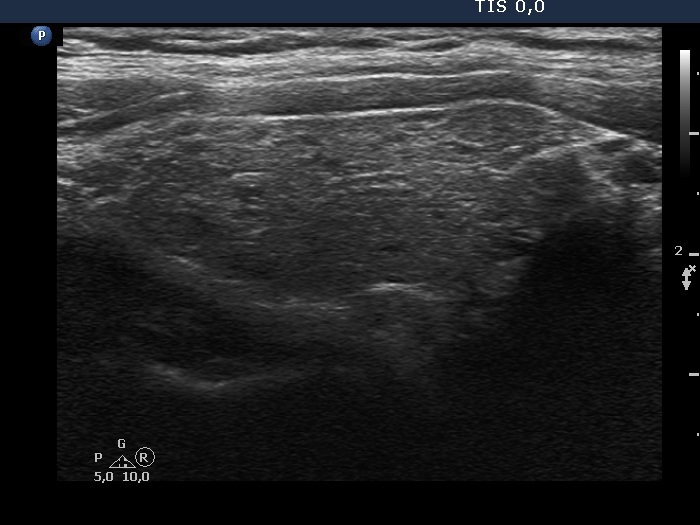

100 consecutive cases of papillary cancer - case 085

Follow-up investigation 7 years after the first visit (ultrasonographic picture 2)

Right lobe, longitudinal scan. Note pronounced fibrotic changes.